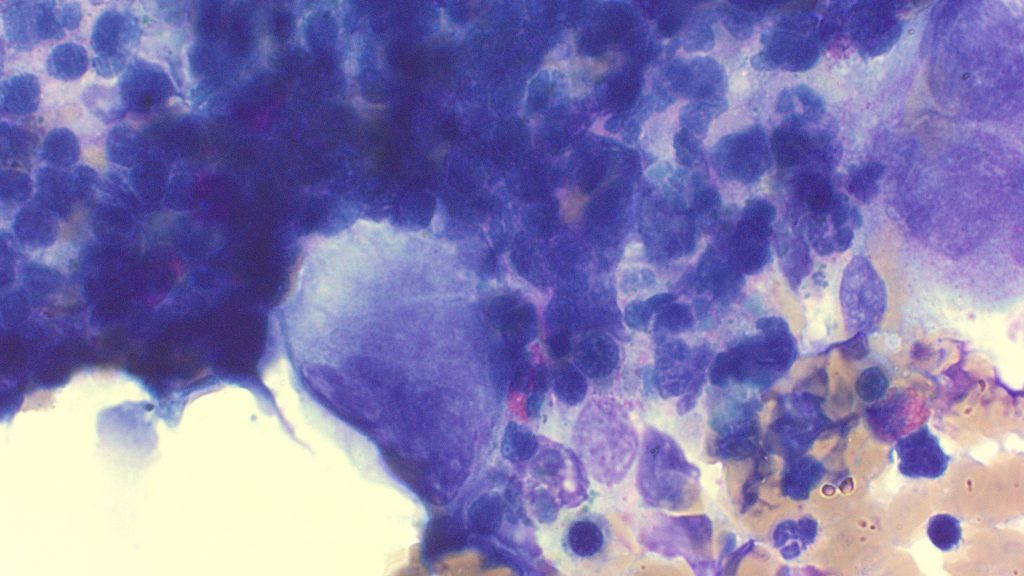

Multiple Myeloma

Myeloma Cells